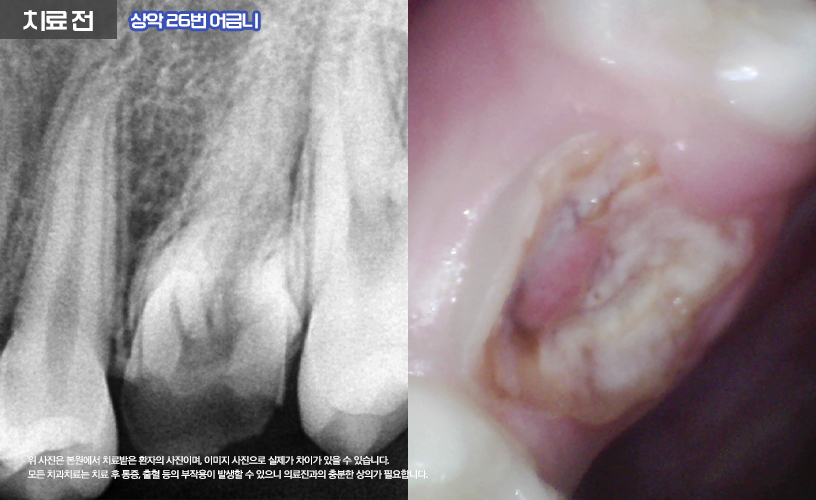

나머지 상, 하악 16,26,36,46번 치아는

신경치료를 통해 치료가 진행됩니다.

먼저 충치로 인해 파절의 정도가 심한 상태이기

때문에 신경치료와 함께 포스트+레진 코어를 통해

얼마 남지 않은 치아의 기둥을 세워

튼튼하게 잡아주었습니다.

또한 환자분의 경우 우식이 깊은 상태였기 때문에

치관의 모양이 상실된 상태에서 우식이

치은연하(잇몸 아래)으로 진행되어

신경치료 전 치은 절제술까지 함께 진행되어

치관의 길이를 확보하는 시술이 추가되었습니다.